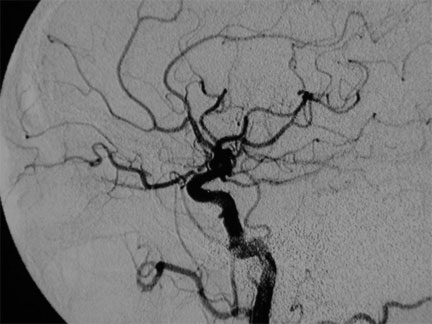

Antes del tratamiento por embolización de fístula carótidocavernosa. Observe la severa dilatación de la vena oftálmica, responsable de la congestión ocular

Antes del tratamiento por embolización de fístula carótidocavernosa. Note la dilatación de la vena oftálmica responsable de la congestión ocular